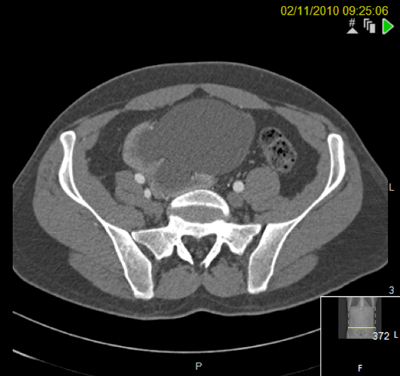

The patient is pain free with no further urinary tract infections postoperatively. The stone is still visible in the retroperitoneum on CT scanning but has caused no further problems 10 years on from surgery.

Seven years postoperatively. New left staghorn calculus and right-sided fragment demonstrated outside the kidney.